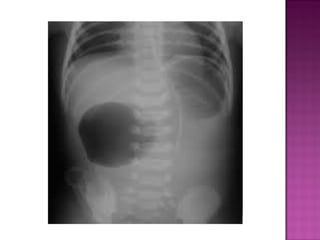

 AXR—gas filled stomach without distal

intestinal air. SINGLE BUBBLE SIGN.

 Rare  Usuallydistal  AXR—gas filled stomach without distal intestinal air. SINGLE BUBBLE SIGN.  Can be dx antenatally on ultrasound.